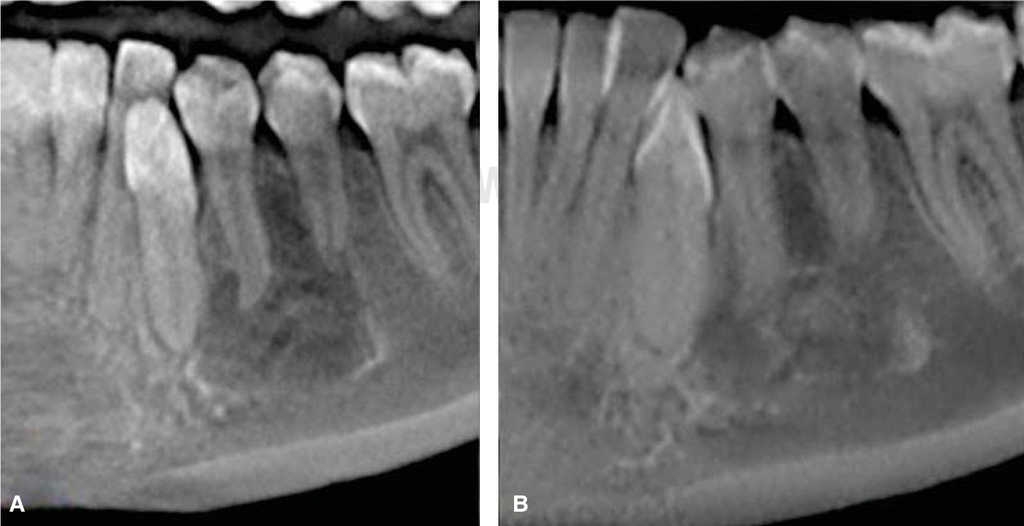

Orthopantomography revealed a radio-lucid lesion, with an irregular border and radio-opaque halo. The lesion involved first premolar, second premolar, and lower left canine, no root resorption or displacement was observed. The lesion exhibited a festooned border in the area of involved dental roots (Figures 2 and 3) and did not present expansion of cortical bone, nevertheless it exhibited thinning in lingual and vestibular cortical bone (Figure 4).

Figure 4 Cross-sectioned cut of the lesion showing thinning of lingual and vestibular cortical bone, without exhibiting expansion.

The lesion extended along the mandibular body without causing bone expansion; lower buccal and lingual cortical bone became thinner (Figure 4). There was no displacement of adjacent teeth towards the lesion; teeth responded positively to vitality tests. These data concur with those reported by Chrcanovic's30 and Xanthinaki's11 clinical case studies. Microscopic study revealed trabecular bone lacking significant histological data, such as mentioned by Harnet et al.9